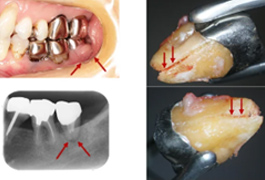

ももこ歯科の精密根管治療は、ペンエンドスタディクラブインジャパンのレギュラーコースで学んだコンセプトに基づいて行なっています。ペンエンドスタディクラブインジャパンのレギュラーコースは、米国で最も古い歯内療法科の一つであるペンシルバニア大学歯内療法科の大学院プログラムをコンパクトにまとめたもので、1年間日本で学べます。このプログラムの講師陣が最重要項目だ、と強調されていたことは、精密根管治療における診査診断と意思決定力です。診査診断と意思決定力が養われてこそ、精密根管治療の技術が向上します。

大きな虫歯で神経をとった方がいい(根管治療を受けた方がいい)といわれた方は、精密根管治療を受けるとその後の歯の状態にトラブルが少なく有意義だと思います。それから、抜歯を提案された方、根管治療がなかなか終わらず不安を抱えていらっしゃる場合、どうしても歯を残したいというご希望がある方は、ぜひ一度ももこ歯科にご連絡ださい。かかりつけ医がいて、根管治療をももこ歯科で受けたい方、セカンドオピニオンをご希望の患者様は紹介状持参でお願いしています。